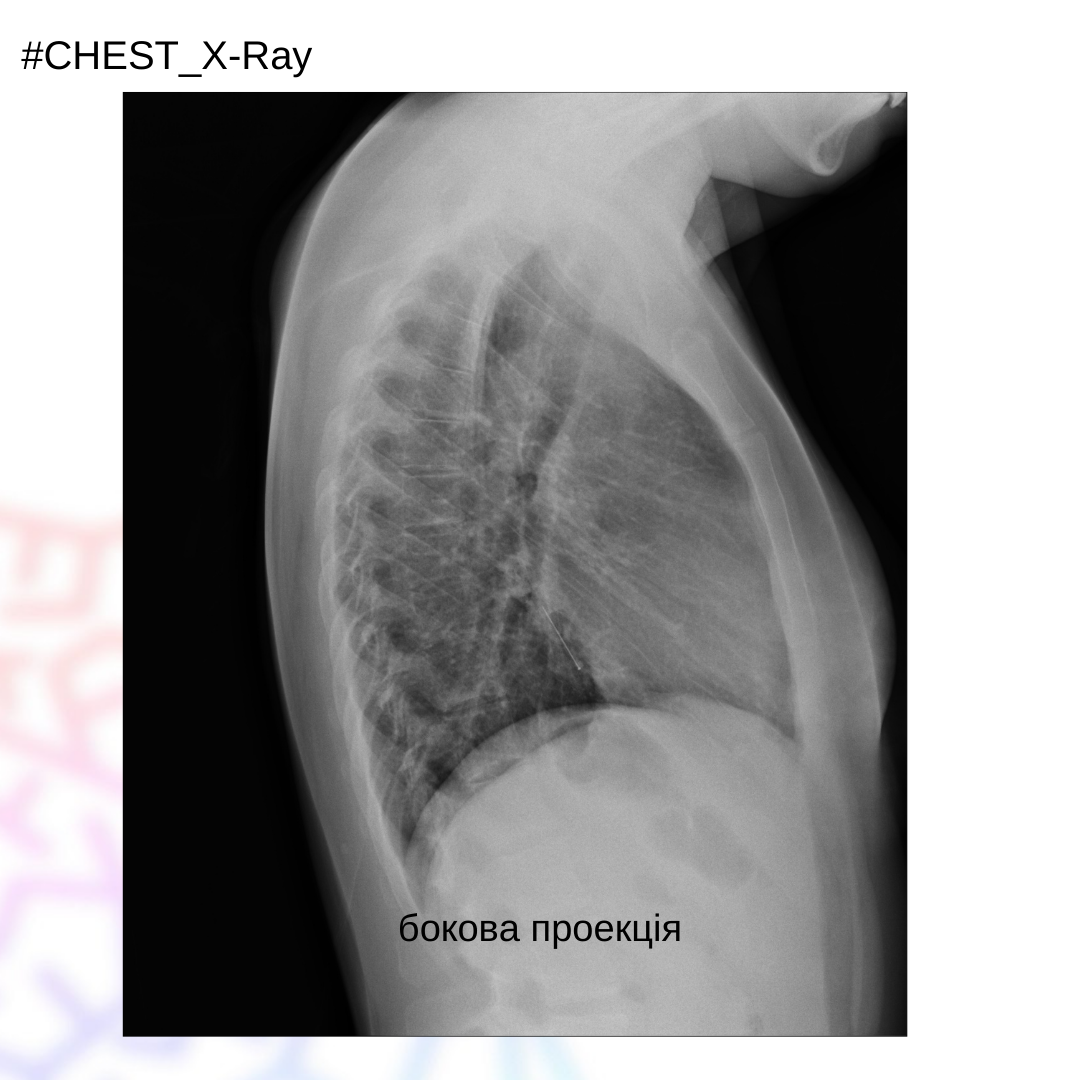

Жінка 30 років, зі скаргами на кашель, задишку, появу хрипів, які виникли після вдихання голки під час шиття.

На рентгенограмі ОГК в прямій та боковій проекціях візуалізується стороннє тіло у передньобазальному сегменті лівої нижньої долі. Пневмоторакс не візуалізується.

Висновок: аспірація сторонніх тіл до дихальних шляхів діагностується на ранніх стадіях, оскільки це викликає такі симптоми, як задишка, хрипи, кашель як у цього пацієнта. У деяких випадках діагностика може бути складною через відсутність типових симптомів або якщо чужорідне тіло не рентгеноконтрастне.